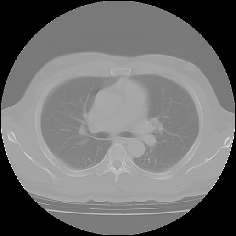

CTやMRIなどの医療機器によって生成されたスライスシリーズ画像を表示する場合、MPR(多断面再構成)表示法は、非常に有効な読影方法であり、特に任意角度の斜断面画像の再構成(Oblique)表示法は、臨床診断に非常に有用かつ重要な読影手法となっています。

ImageClarityのMPR表示機能は、エンジンレベルで実現したもので、任意空間原点と任意3D方向の断面を表示することが可能になっており、補正表示をしながら実用レベルの高速表示を実現し、3D処理開発キットとしても非常に利用しやすいAPIを提供しています。 MPR以外に、任意サイズのMIP(最大値投影)表示法もサポートしています。

MPR/MIP表示